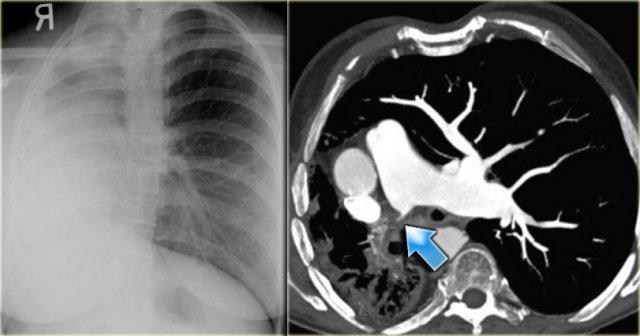

On the left a chest film of a young adult with a cough.

There is a right paratracheal mass.

The differential diagnosis is tumor, adenopathy or vessel (right arch, dilated azygos vein, dilated aberrant right subclavian artery).

On the left axial images and posterior view of volume rendered reconstruction.

Describe the findings and then continue.

The findings are:

- four vessel sign

- double arch

- right arch higher and larger

- esophagus and trachea are completely encircled

The narrowing of the trachea is seen on the axial images, but better appreciated on the MPR and Volume Rendered image.